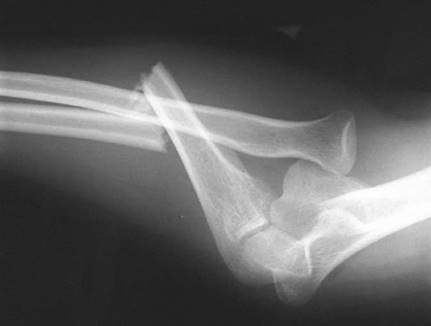

Can you describe the injury to me?

This is an AP radiograph of the right elbow showing a Monteggia fracture dislocation. I would like to see further views of the whole forearm as well as a lateral view of the elbow to determine the exact direction of dislocation of the radial head.

How do you classify these types of injury?

C lassifi cation of Monteggia fractures is using the Bado system and is determined by the direction of radial head dislocation:

1. Anterior 70โ€“85 %

2. Posterior (5 % ; more common in adults than children)

3. Lateral (15โ€“25 % )

4. Any: with associated radial shaft fracture (rare)

How would you manage this patient?

Management of this isolated injury can be divided into initial A&E management and defi nitive management. I would fi rst assess the patient in A&E giving some analgesia and taking a full history. On examination I would check the soft tissues for any evidence of open fracture or compartment syndrome as well as documenting carefully the distal neurovascular status. The posterior interosseus nerve is particularly at risk. This fracture dislocation needs to be reduced and fi xed urgently. I would organize for the patient to go to theatre when medically safe. In theatre I would use a direct approach to the ulna shaft utilizing the internervous plane between extensor carpi ulnaris (ECU) (posterior interosseous nerve, PIN) and fl exor carpi ulnaris (FCU) (ulnar nerve, UN). I would reduce the fracture under direct vision and then check with an image intensifi er whether the radial head had relocated. I would fi x this fracture with a 3.5-mm dynamic compression plate using AO principles.

You choose to open and reduce the ulna fracture under direct vision and fi x it with a dynamic compression plate. Tell me how this plate works.

Compression can be applied across the fracture in a number of diff erent ways. Firstly by pre-bending the plate; secondly by placing the screws eccentrically in the combihole to allow sliding compression at the fracture site; and thirdly by utilizing the compression device via a separately placed screw adjacent to the plate.

P ost-operatively I would protect the soft tissues in a backslab for 4 weeks to prevent late subluxation of radial head. The patient would then require physiotherapy to regain elbow motion.